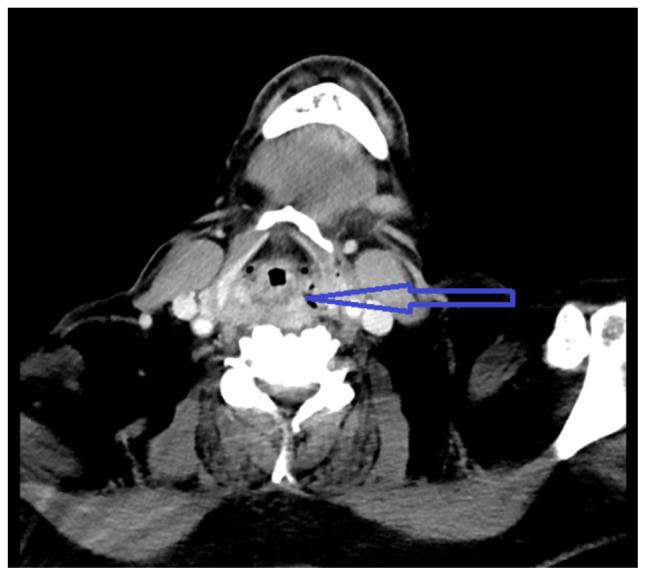

Transesophageal echocardiography is a relatively safe procedure; however, there are rare complications associated with it. Multiple attempts during TEE can lead to injury of hypopharyngeal or parapharyngeal wall leading to an infection. Here, we describe a case of hypopharyngeal-parapharyngeal abscess resulting from multiple TEE attempts during cardioversion leading to a prolonged hospital course.

经食管超声心动图检查是一种相对安全的检查方法;然而,它也存在一些罕见的并发症。经食管超声心动图检查过程中的多次尝试可能导致下咽或咽旁壁损伤,进而引发感染。在此,我们描述一例因心脏复律期间多次进行经食管超声心动图检查尝试而导致下咽-咽旁脓肿的病例,该病例导致住院时间延长。